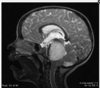

You are called to the NICU to see a 1 day old child who appears as demonstrated in figures 1 and 3. His CT scan is shown in figure 2 He has been stable, although with occasional apnea when agitated. On exam, he has a bulging fontanelle. His parents wish to pursue aggressive care. When should he undergo a cranial vault procedure? a. At 24 months of age b. In the next several days. c. At 6 months of age. d. At 18 months of age e. At 12 months of age

In the next several days.